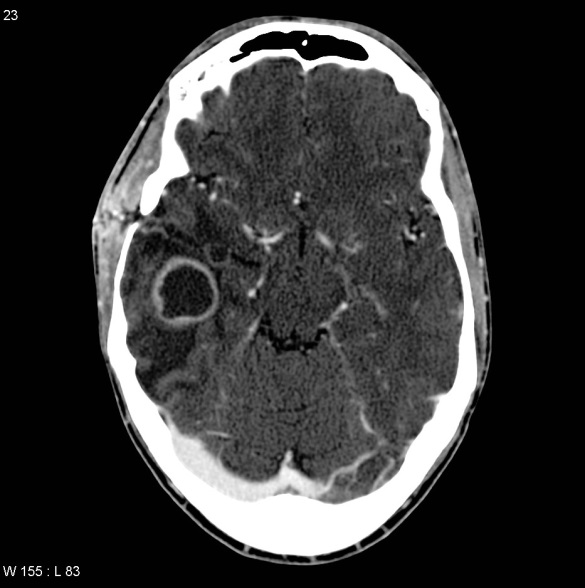

Bron: http://www.slideshare.net/mohamedsshaaban5/brain-infections3

Weefselcyste in hersenen bij de mens

Bron: Prof Frank Gaillard Radiopaedia.org